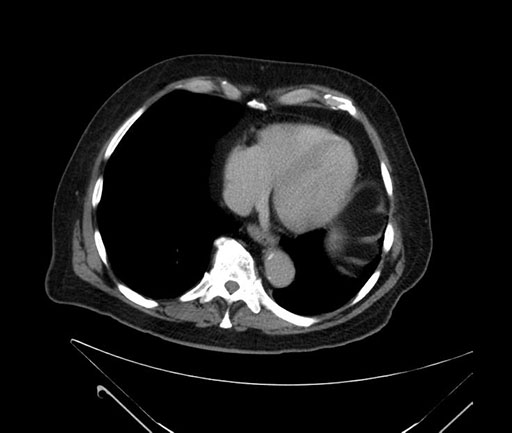

Imaging Analysis

Look through the patient's CT scan to identify any areas of concern for the necessary procedure.

Based on your CT findings, which issue(s) would give reason for "planned slowing down moment(s)" in this case?

Considering a standard Whipple procedure, what step(s) of the operation would you do differently in this case?